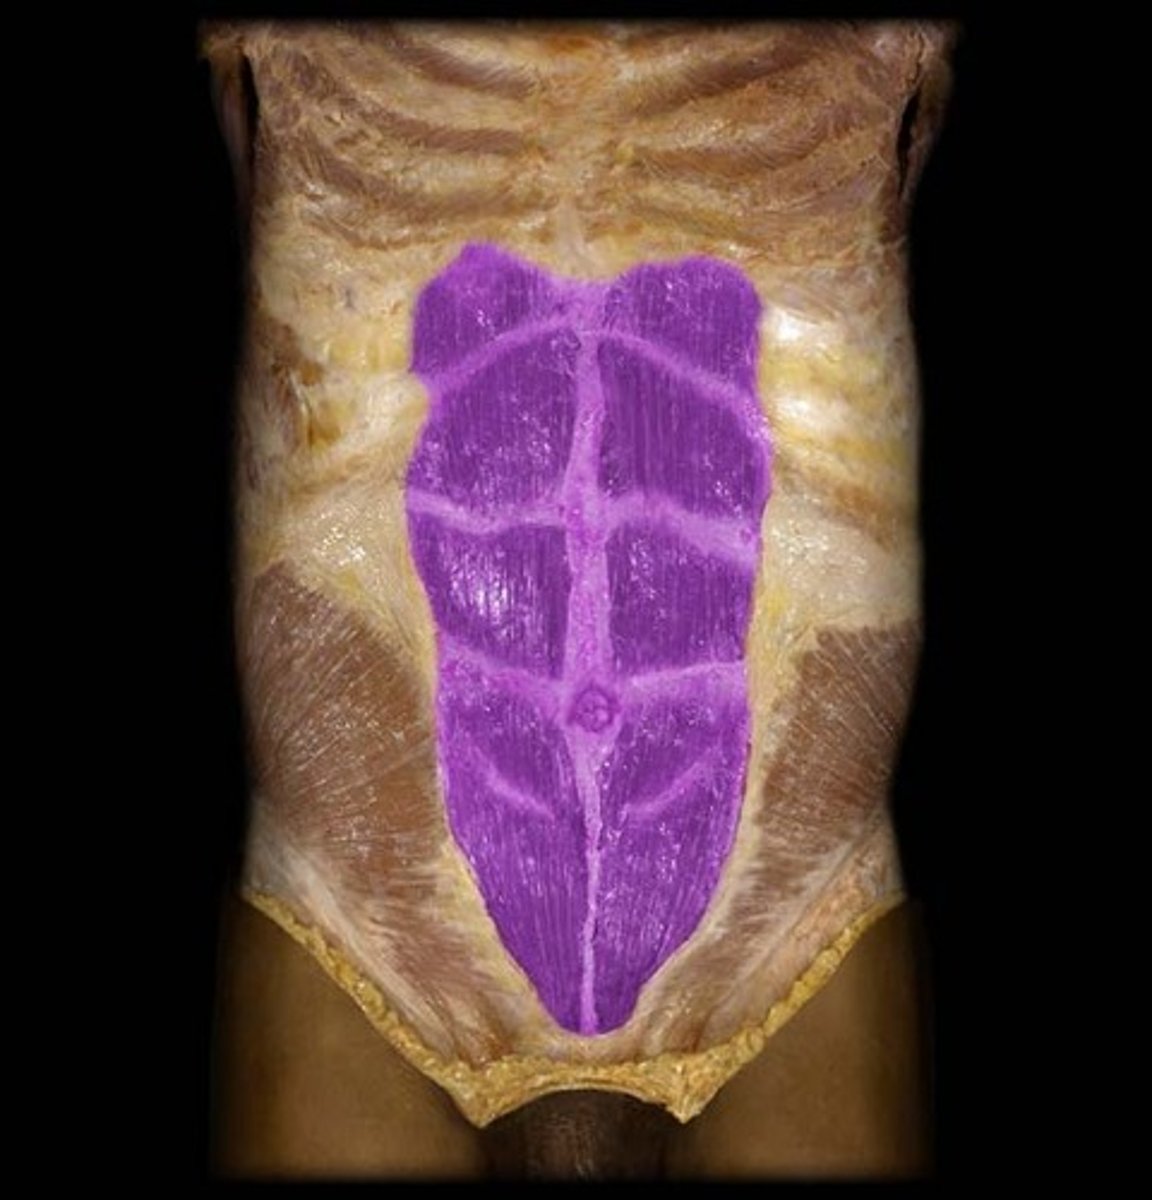

rectus abdominus

tendinous insertions

rectus sheath